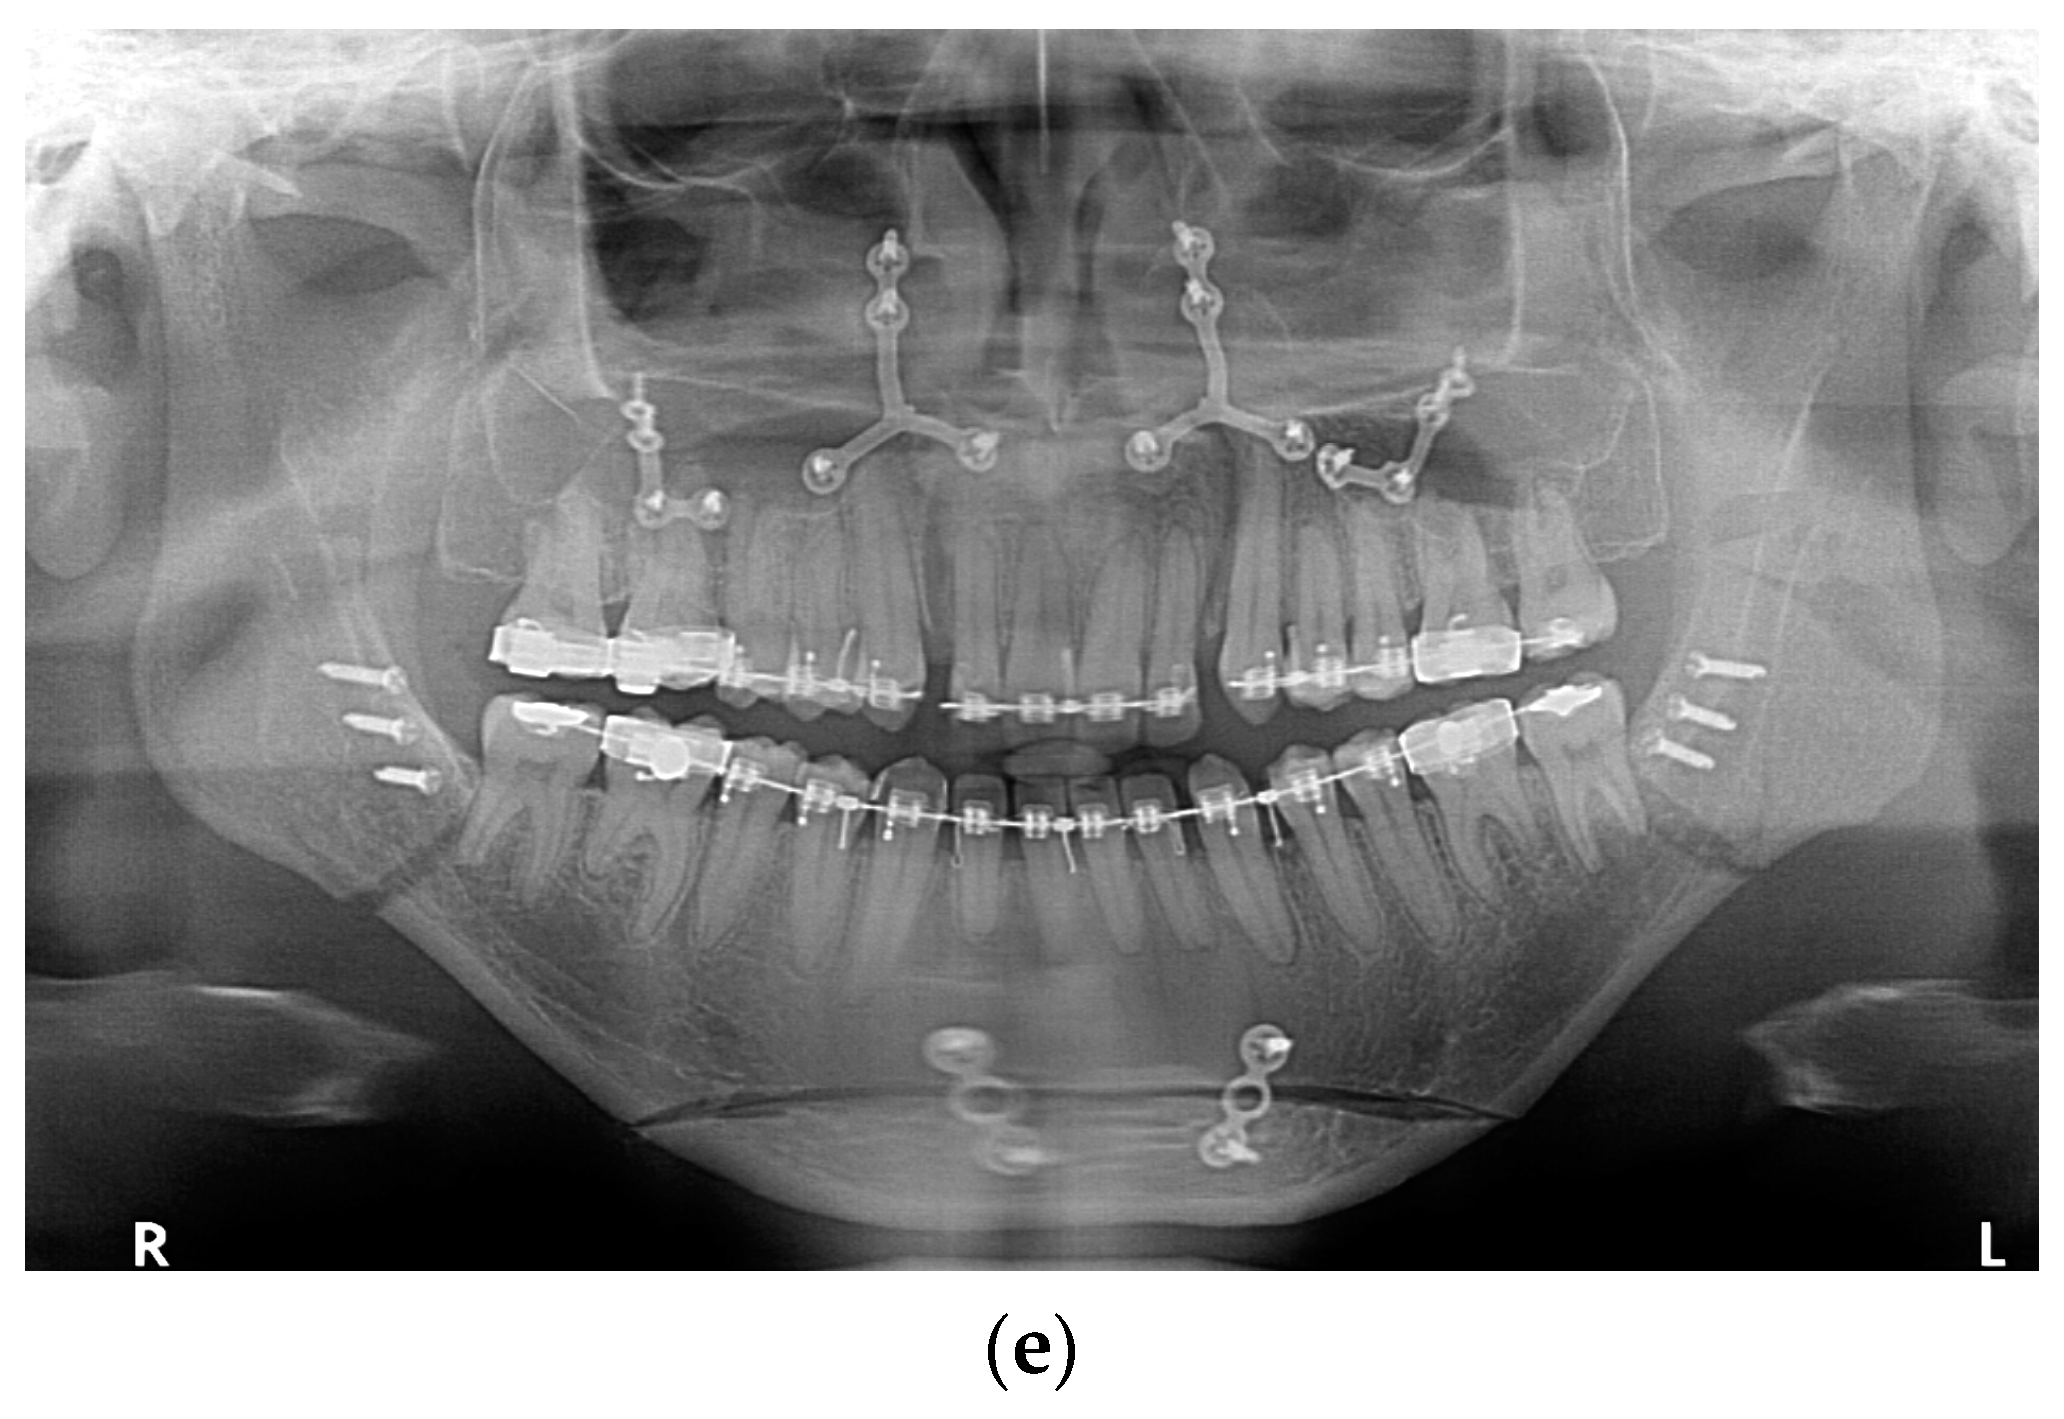

All fixation hardware used in orthognathic procedures was made of titanium (Figure 1).

Figure 1.

Panoramic X-ray with fixation hardware: (a) after BSSO; (b) after BSSO and genioplasty; (c) after Le Fort I osteotomy; (d) after bimax; (e) after bimax with maxillary segmentation and genioplasty.

In the case of sagittal mandibular ramus osteotomy, the typical way to fix the osteotomy fragments was to use one bicortical screw as well as a single plate and monocortical screws on both the right and left side. In a few selected cases, only three bicortical screws were used without a plate, the use of a bicortical screw was abandoned and the fragments were provided fixation using only one plate, and monocortical screws or more than one bicortical screw and a plate were used. Each time it was dictated by individual anatomical and mid-operative conditions. All fixation hardware in the mandible was made with screws that required drilling and were made through an intraoral approach.

In Le Fort I maxillary osteotomy, the osteotomy fragments were typically fixed using 4 plates (most commonly in the shape of the letter “L”; for maxillary segmentation “Y” plates were used) and an appropriate number of monocortical screws. Screws that do not require drilling, i.e., self-drilling screws, were used. In selected situations dictated by anatomical conditions, customized solutions were used in the form of an additional plate, a non-standard shaped plate, or a reduced number of screws.

For genioplasty, dedicated plates with a bridge of appropriate length or two plates bent by the operator according to the planned bone movement were used together with monocortical screws.